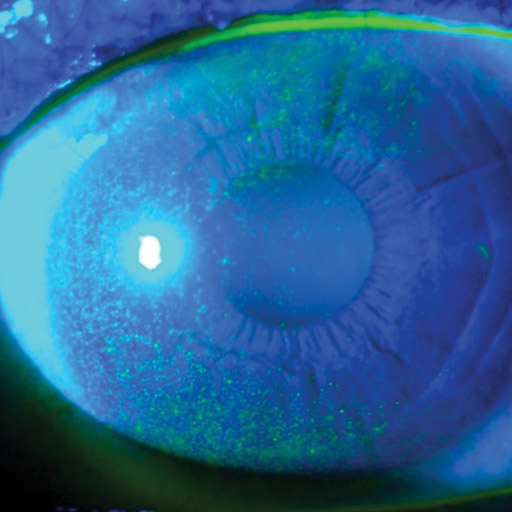

Dry Eye Disease (DED) happens when your eyes don’t make enough tears, or when the tears don’t stay on the eye’s surface long enough.

The tear film normally has three layers (oil, water, and mucin). If any layer is out of balance, your eyes can feel dry, gritty, or irritated.

- Meibomian gland dysfunction (poor oil layer in tears)